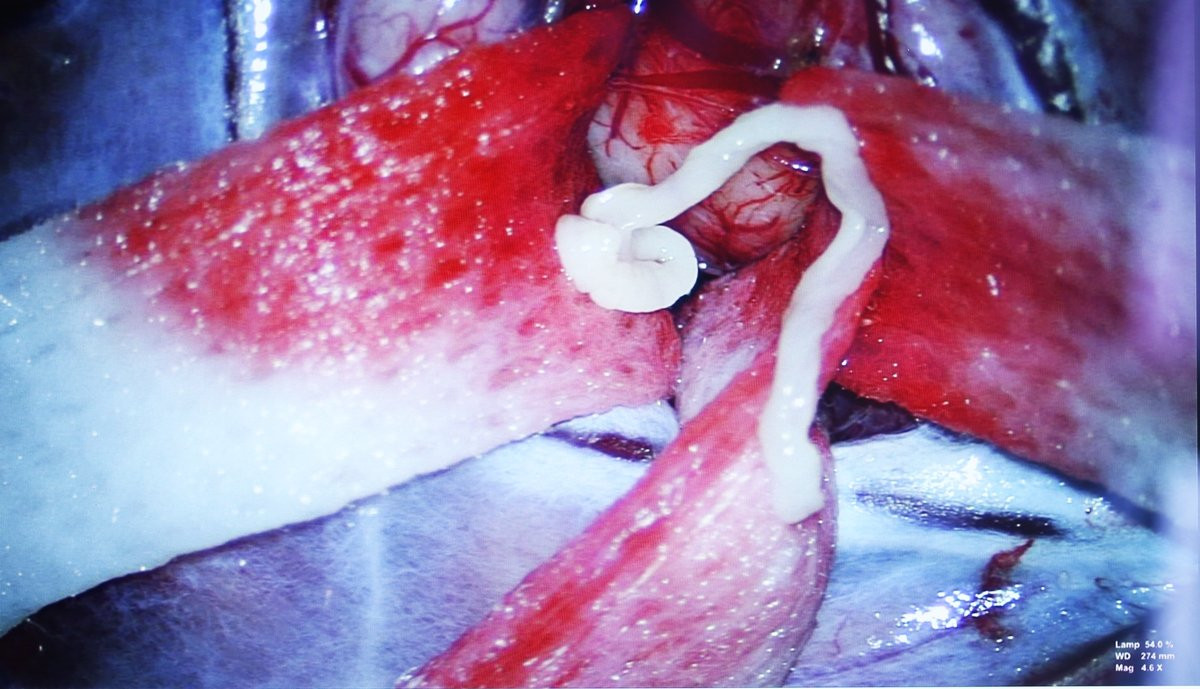

Bác sĩ chỉ định bệnh nhân phẫu thuật. Kíp mổ lấy ra một ký sinh trùng dài khoảng 7cm trong não người bệnh.

Ký sinh trùng trong não bệnh nhân.

Kết quả giải phẫu bệnh cho thấy ký sinh trùng trong não bệnh nhân này có tên khoa học Spirometra erinaceieuropaei hay còn gọi là sán nhái. Người dân có nguy cơ nhiễm khi ăn thịt ếch, nhái, gà, vịt, chim không nấu chín kỹ. Sán nhái thường ký sinh ở mắt người, rất hiếm khi có ở não.